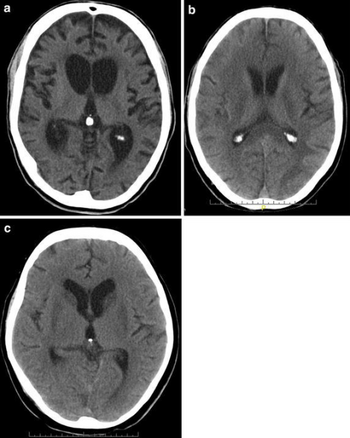

There are several imaging techniques that can aid in diagnosing and assessing the extent of brain damage, such as computed tomography (CT) scan, magnetic resonance imaging (MRI), diffusion tensor imaging (DTI) magnetic resonance spectroscopy (MRS), positron emission tomography (PET), and single-photon emission tomography (SPECT). CT scans and MRI are the two techniques widely used and are most effective. CT scans can show brain bleeds, fractures of the skull, fluid build up in the brain that will lead to increased cranial pressure. MRI is able to better to detect smaller injuries, detect damage within the brain, diffuse axonal injury, injuries to the brainstem, posterior fossa, and subtemporal and subfrontal regions. However, patients with pacemakers, metallic implants, or other metal within their bodies are unable to have an MRI done. Typically the other imaging techniques are not used in a clinical setting because of the cost, lack of availability.[36]